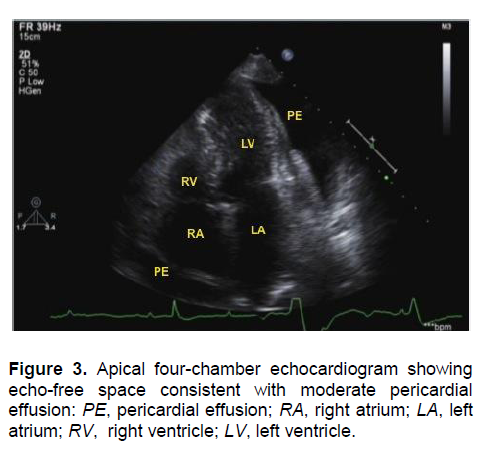

A 2D-echocardiogram showed left ventricular hypertrophy, normal right ventricular dimension with evidence of diastolic collapse noted at the right ventricular outflow tract (RVOT), normal right and left atrium, moderate pericardial effusion mostly noted in the lateral portion of the left ventricular free wall with signs of tamponade physiology (Figure 3). A tube pericardiostomy drained 890 mL of straw-colored pericardial fluid. The pericardiostomy tube was removed on the 3rd post-operative day. Cytological examination of the pericardial fluid did not reveal bacterial or viral infection. There were no malignant cells or granulomas seen on examination of the pericardial tissue.

Click here to download Figure 3

Figure 3. Apical four-chamber echocardiogram showing echo-free space consistent with moderate pericardial effusion: PE, pericardial effusion; RA, right atrium; LA, left atrium; RV, right ventricle; LV, left ventricle.

Pericardial effusion in hypothyroidism is related to the severity and duration of the disease. Its incidence is reported to be at 3% in early mild stage to 80% when myxedema is present.9-10 The occurrence of cardiac tamponade in hypothyroidism is uncommon due to the slow accumulation of fluid and the remarkable distensibility of the pericardium.11 The classic signs of hypotension, muffled heart sounds, jugular vein distention and pulsus paradoxus are not always present.12 The compensatory tachycardia in a patient with tamponade is usually absent in hypothyroidism, as in our case. Many hypothyroid patients have high serum CK concentrations. The isoenzyme distribution is almost completely MM, with less than 4% constituting MB, indicative of skeletal muscle origin.13 ECG may reveal low-amplitude QRS complexes, prolonged QT interval, and flattened or inverted T waves. Echocardiography remains the most reliable diagnostic modality with exceptionally high specificity and sensitivity.14 Echocardiographic features of tamponade include chamber collapse and reciprocal changes in left and right ventricular volumes with respiration.12 Pericardial fluid exceeding 25-50 ml is seen as an echo-free space through-out the cardiac cycle signifying pericardial effusion.